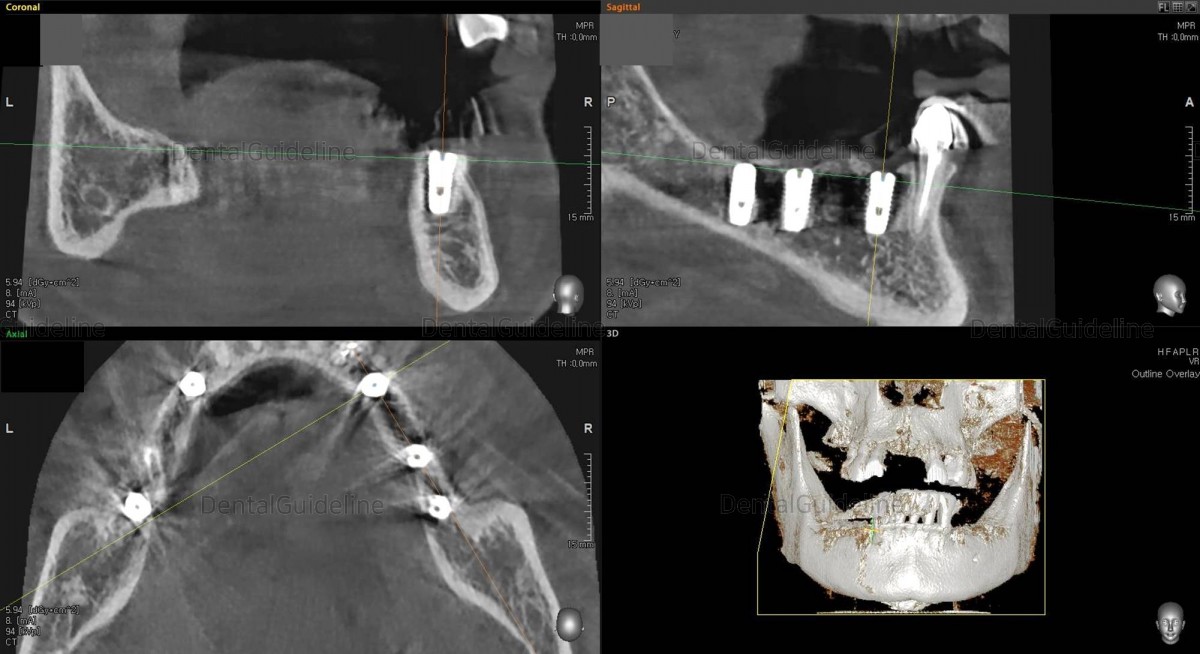

CBCT scan Arum NB-1 Ø4.5/ L10

(20Ncm) at

the 2nd molar zone.Arm Dentistry NB-1 Ø4.5/ L10

the 2nd molar zone.Arum Dentistry NB-1 Ø4.5/ L10

the 2nd molar zone.